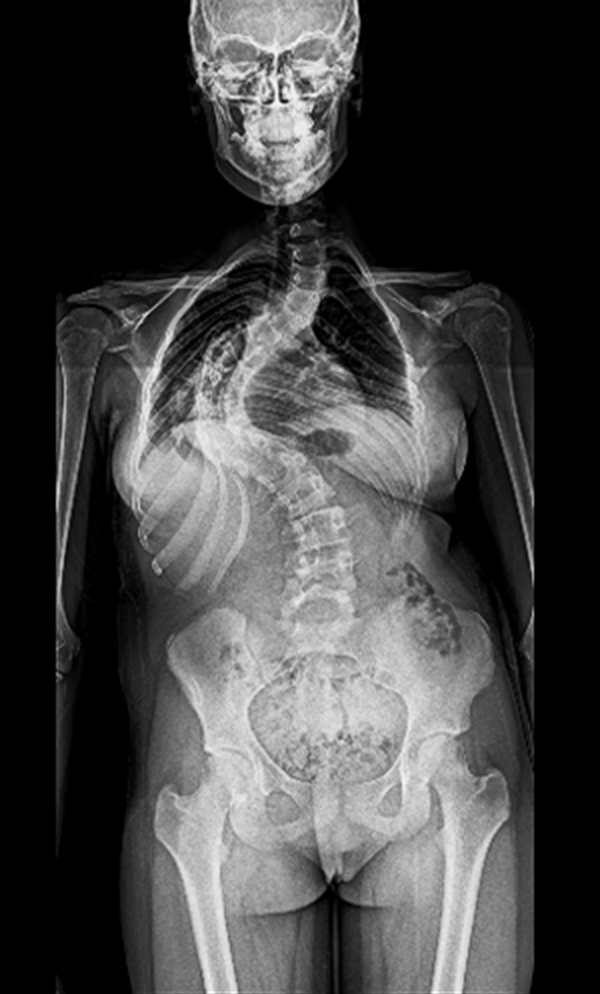

BEYOND RECOVERY : REAL STORIES

Gallery : Before - After